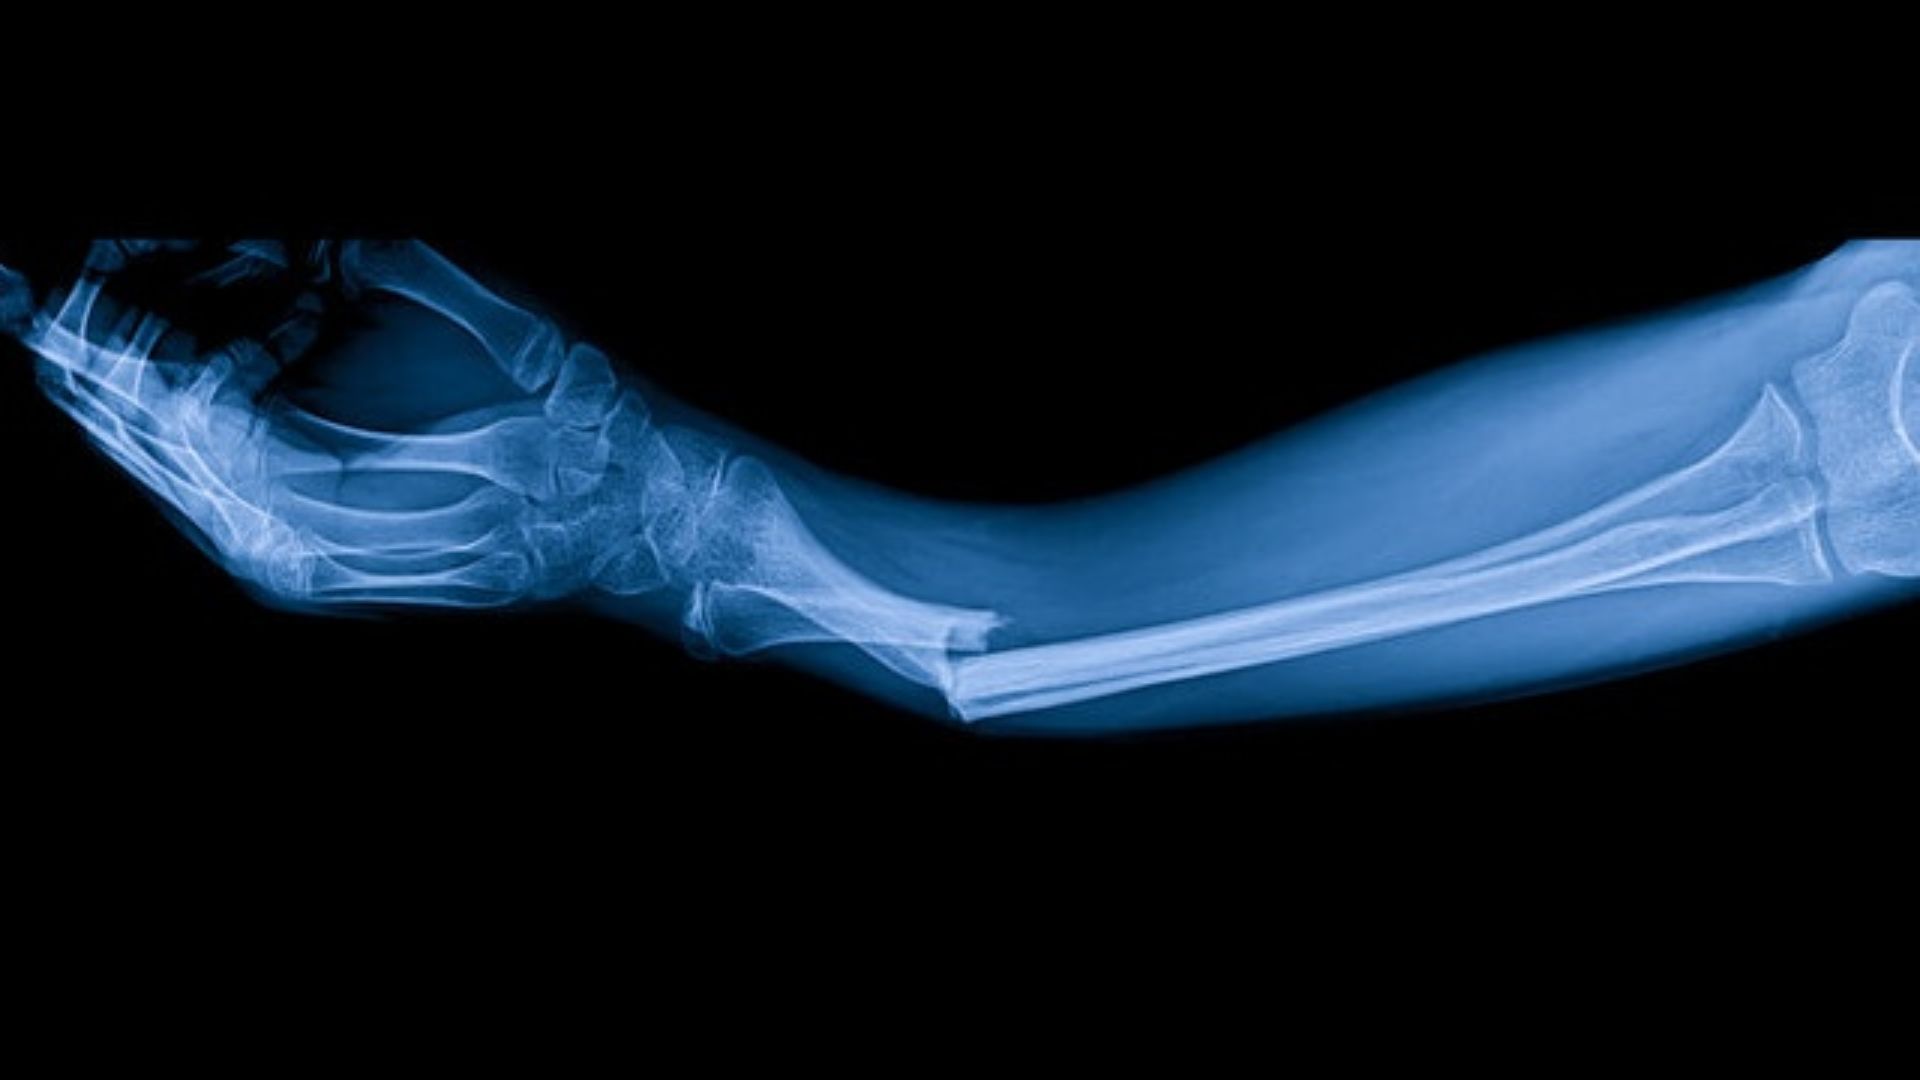

Xương cánh tay là xương dài duy nhất ở phần cánh tay trên, được xem là xương lớn nhất và chắc chắn nhất của toàn bộ chi trên. Nó có cấu trúc vững vàng để chịu lực nén và xoắn lớn từ các hoạt động hàng ngày đồng thời đóng vai trò trụ cột chính giúp cánh tay thực hiện các động tác phức tạp. Nhờ độ dài và độ dày phù hợp, xương cánh tay hỗ trợ toàn bộ trọng lượng khi nâng vật nặng hoặc thực hiện các môn thể thao đòi hỏi sức mạnh chi trên.

Xương cánh tay nằm giữa khớp vai và khớp khuỷu tay, nối trực tiếp xương vai với hai xương cẳng tay là xương quay và xương trụ. Nó tham gia trực tiếp vào cấu tạo khớp vai ở đầu trên và khớp khuỷu ở đầu dưới, tạo thành cầu nối quan trọng cho toàn bộ chi trên. Bạn có thể dễ dàng cảm nhận xương cánh tay bằng cách sờ dọc từ vai xuống khuỷu tay. Đây là phần xương nổi rõ dưới da ở mặt ngoài cánh tay.

Xương cánh tay có cấu tạo điển hình của xương dài, được chia thành ba phần chính với các đặc điểm giải phẫu riêng biệt. Nhờ vậy mà xương cánh tay thực hiện tốt chức năng chịu lực và vận động linh hoạt.

Gãy xương cánh tay thường xảy ra do té ngã chống tay, tai nạn giao thông hoặc chấn thương thể thao như bóng đá, trượt tuyết. Tình trạng này hay gặp ở người cao tuổi do loãng xương làm xương giòn hơn và trẻ em hiếu động. Biểu hiện của gãy xương cánh tay bao gồm đau dữ dội, sưng nề, biến dạng cánh tay và hạn chế vận động nghiêm trọng, cần bất động hoặc phẫu thuật để hồi phục.